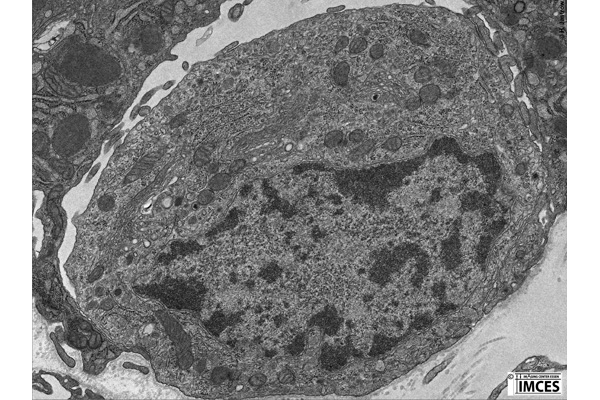

Transmissionselektronenmikroskopisches Demonstrationsbild (Aufnahme: H. Jastrow) JEOL 1400 Plus TEM

Dieses transmissionselektronenmikroskopische Bild zeigt eine Kalzitonin-bildende C-Zelle der Schilddrüse mit ihren Organellen.